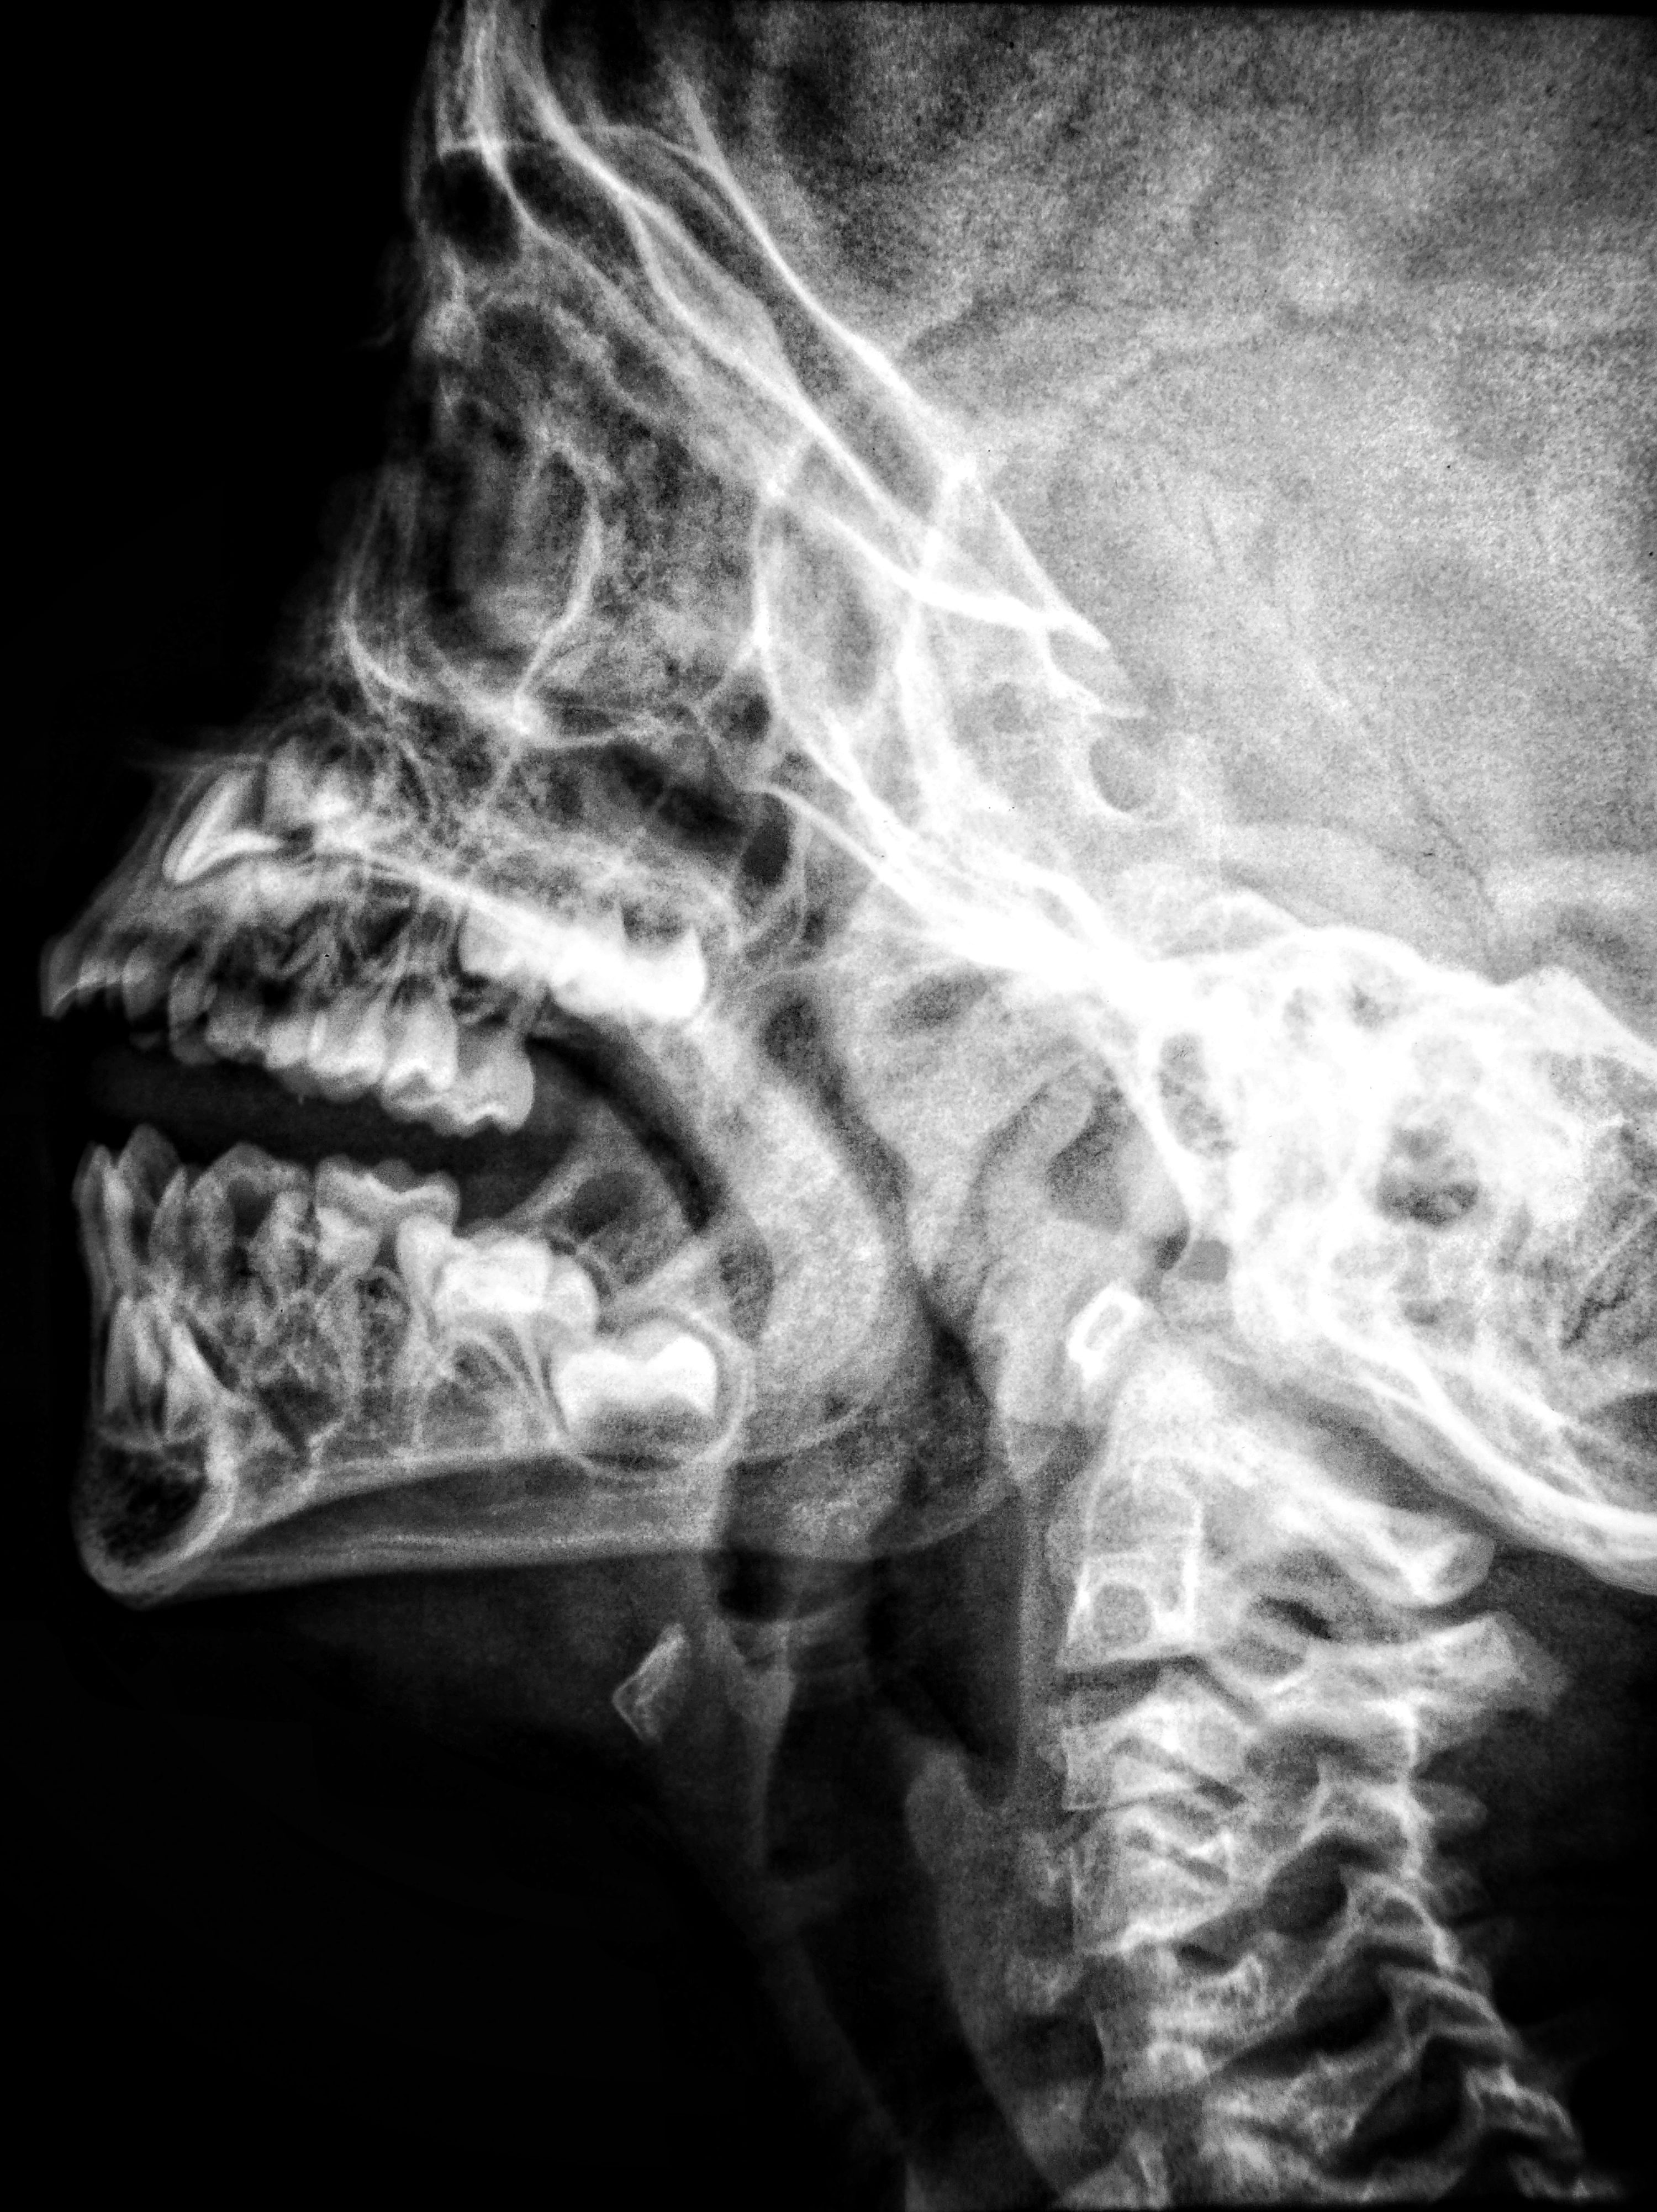

- 임플란트는 잇몸뼈라는 '땅'에 나사를 박는 공사입니다. 땅이 단단하고 깊어야 건물이 서겠죠? 치주염으로 잇몸뼈가 녹아내려 얇아진 경우에는 인공 뼈 가루를 채워 넣는 **'뼈 이식'**이 필수적입니다. 안 그러면 나사가 흔들려서 빠져버립니다.